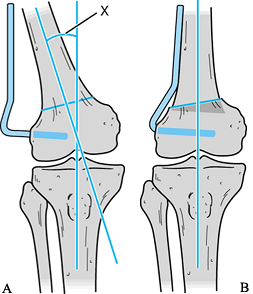

degree of correction is not well established (32). Both Coventry (8)and Morrey and Edgerton (36)

preoperative films (Fig. 107.5A). Sterilize the

95° blade plate to hold the osteotomy. Staples are not adequate (8,36). The angle of the template must be increased by 5° if a 95° blade plate is to be used.

Figure 107.5. A:

Distal femoral osteotomy by the medial approach. The degree of valgus alignment (X) is calculated from standing long-leg films. Place Steinmann pins in the sequence outlined in the text. The wedge osteotomy is represented by the shaded segment. Undercutting the angle allows impaction of the proximal segment into the distal segment. B: Apply the blade plate medially. |

Under fluoroscopic guidance, drill a guide pin for the blade plate chisel across the femur 2.5 cm proximal to the condyles (107.5A,1).

perpendicular to the femoral shaft proximal to the osteotomy site (107.5A,2). Use a third pin to reproduce the desired angle of correction in relation to the perpendicular, proximal pin (Fig. 107.5A,4).

Place this pin between the first two pins. The prefabricated angle